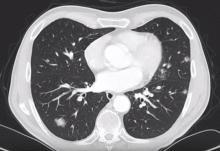

A 65-year-old male patient with metachronous metastatic supraglottic carcinoma was admitted for metastasectomy after a complete resection of the primary tumor and adjuvant radio-chemo therapy. Metastasectomy was conducted in two stages. First, the patient underwent left-sided anatomical lingular resection for two metastases, together with a wedge resection of another metastasis in the lower lobe. After a recovery phase, he then underwent a right-sided metastasectomy. The postoperative course was event-free, and the patient was discharged on the fourth postoperative day.